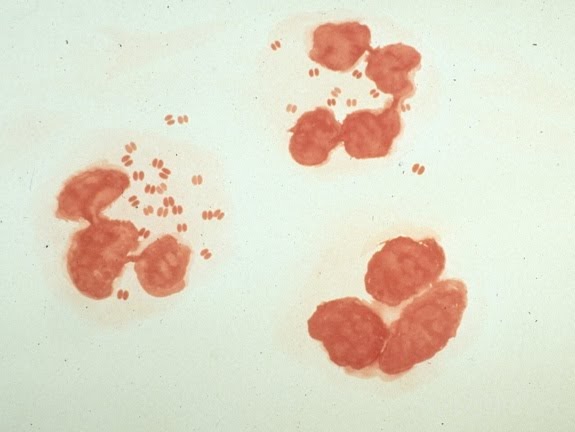

Neisseria Gonorrhoeae Is The Causative Agent Of Gonorrhea ... 😈